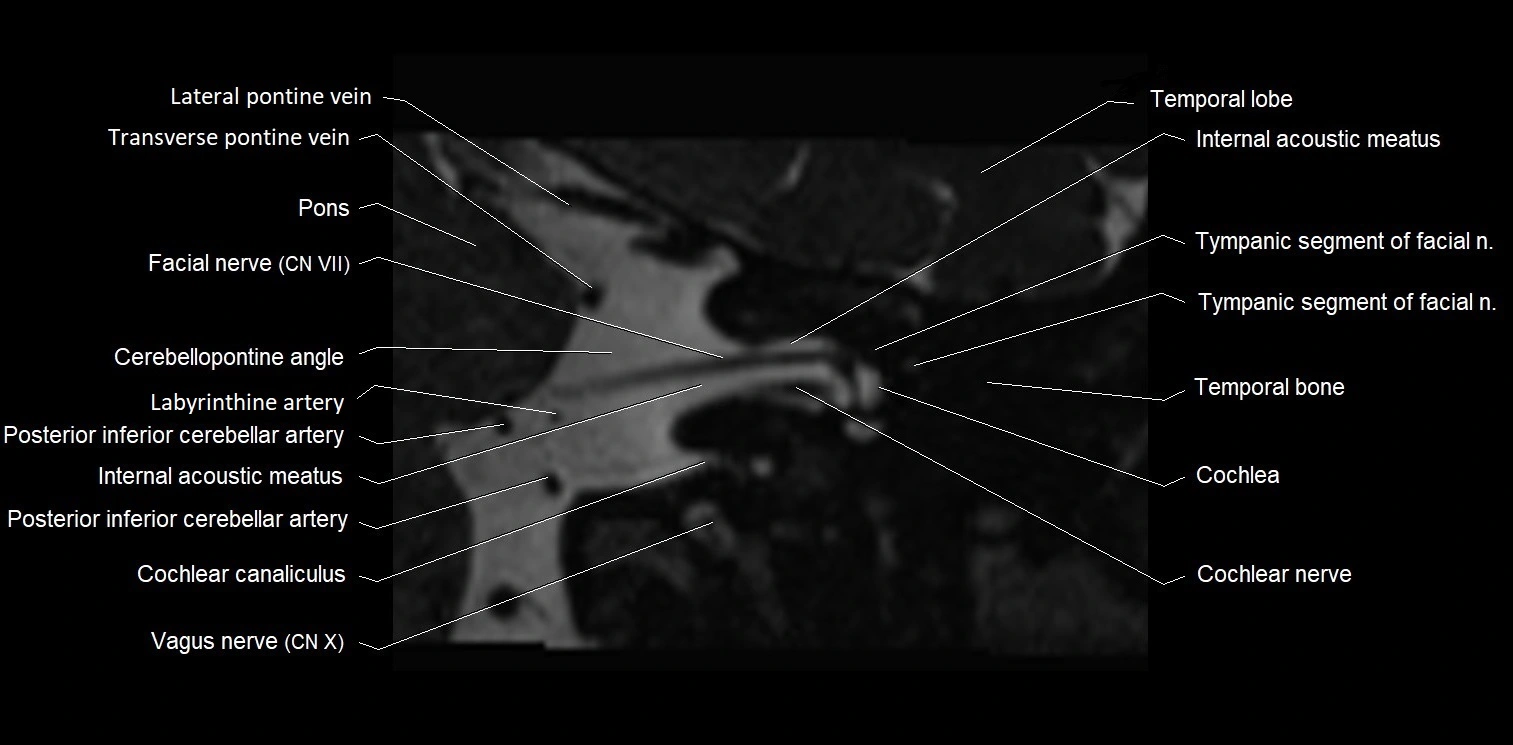

MRI Appearance

• The abducens nerve is a small, thin, linear structure

• Best visualized on high-resolution T2-weighted 3D MRI sequences (e.g., FIESTA or CISS)

• Seen as a hypointense (dark) line running from the brainstem at the pontomedullary junction, traversing the prepontine cistern, and entering Dorello’s canal under the petrosphenoidal ligament, then into the cavernous sinus, and finally the orbit

• May be challenging to visualize in standard MRI due to its small size

• Pathology may be inferred by absence, displacement, or enhancement of the nerve